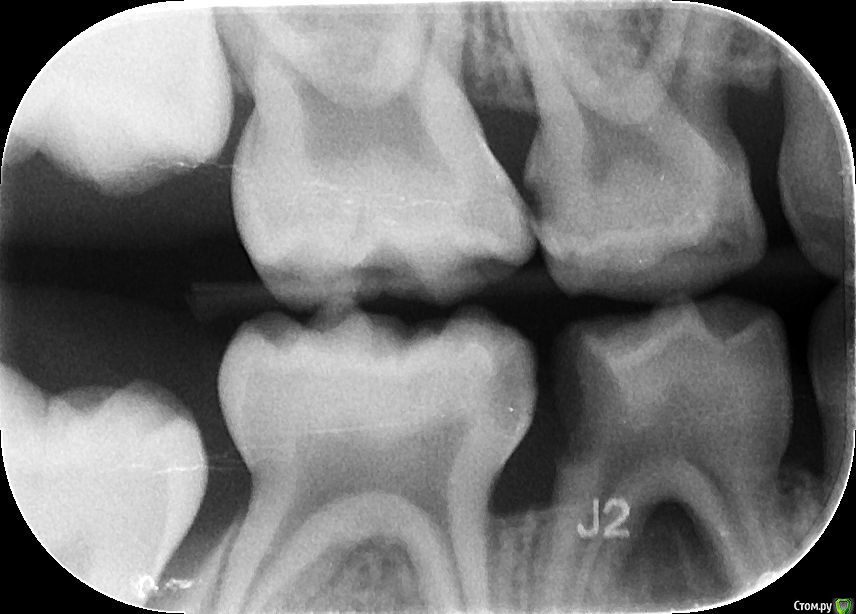

Elena Bundren Опубликовано 27 июня, 2018 Поделиться Опубликовано 27 июня, 2018 Здравствуйте!Пришли с 5-летним ребенком к стоматологу. Он обнаружил 12 кариесов, сказал, на несколько зубов надо ставить серебренные коронки.Моляр справа внизу подлежит удалению, так как под ним инфекция.И все это хорошо бы сделать под общей анестезией за один раз.Вопросы уважаемым докторам, сколько, по-вашему, зубов реально подлежит лечению, и есть и возможность, на ваш взгялд, сохранить моляр, если да, то какое нужно лечение.Также, каково ваше мнение об общей анестезии для ребенка 5 лет. Ссылка на комментарий

St. Опубликовано 27 июня, 2018 Поделиться Опубликовано 27 июня, 2018 Добрый день. Зубы действительно в очень плохом состоянии и практически на всех между зубами есть кариес.Металлические коронки у детей это хорошо, они позволяют надежно провести лечение сильно разрушенных зубов и не опасаться сколов и вторичного кариеса. Ссылка на комментарий